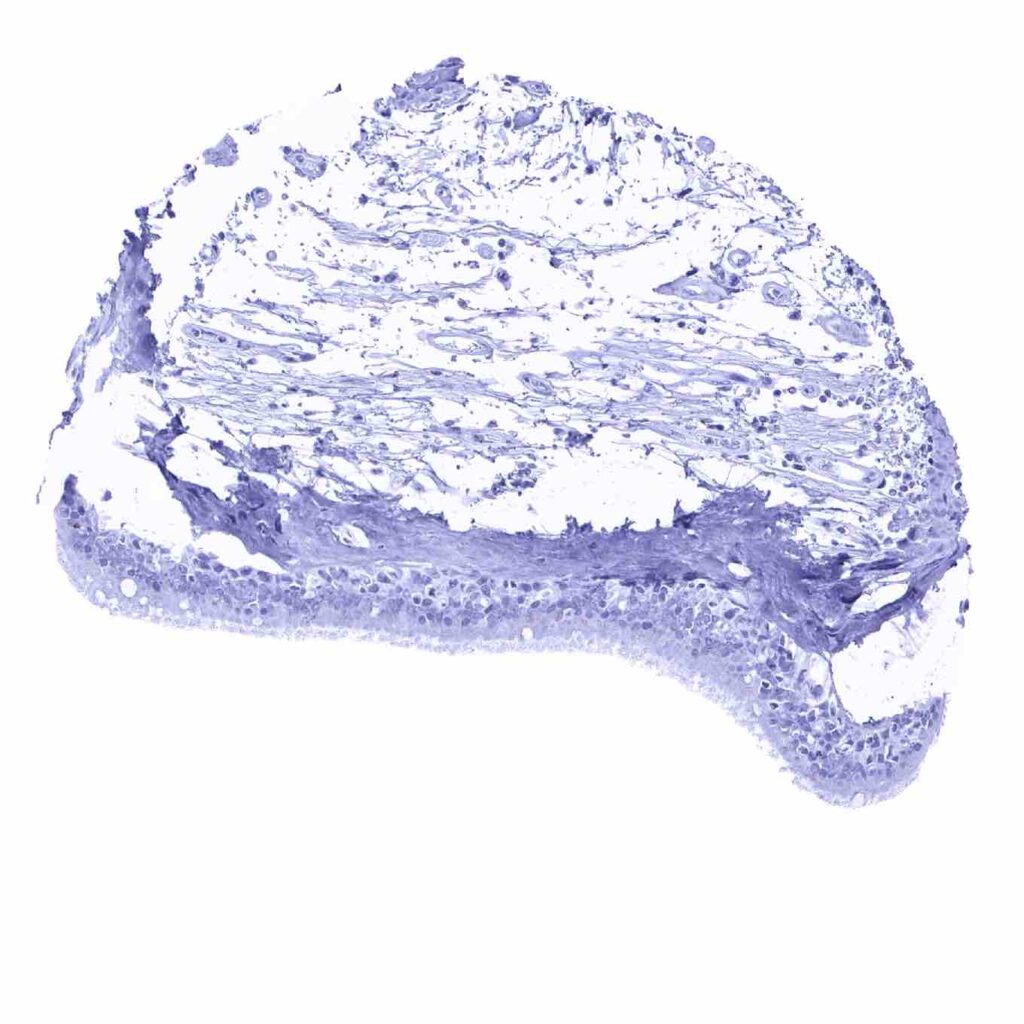

Cerebellum (molecular layer, Purkinje cell layer, granule cell layer, white matter)